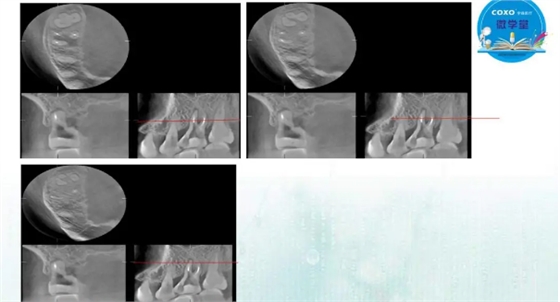

主任医师,牙体牙髓副主任, 广东省口腔医院牙体牙髓科 主任医师。2003年硕士研究生毕业,研究方向为牙体牙髓病学,擅长于牙体牙髓病的诊断、龋齿、牙髓炎、根尖周病的治疗以及前牙美容修复。